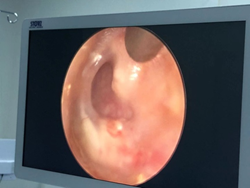

耳内镜提示:左侧鼓膜穿孔